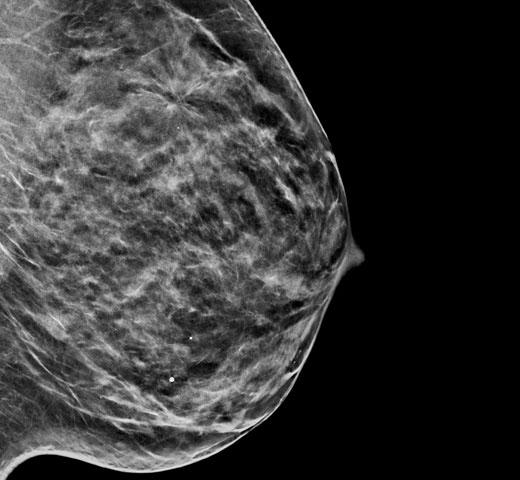

Contrast Enhanced Mammography (CEM), the imaging of a breast using iodinated contrast to reveal areas of increased blood supply within the breast, can help enhance suspicious lesions. The I-View software can combine the power of CEM with 2D and tomosynthesis images, all under one compression, providing anatomical and functional imaging in one exam.1

This software captures both anatomical and functional information in a single exam by leveraging our ability to provide 2D, contrast and tomosynthesis images in just one compression.1